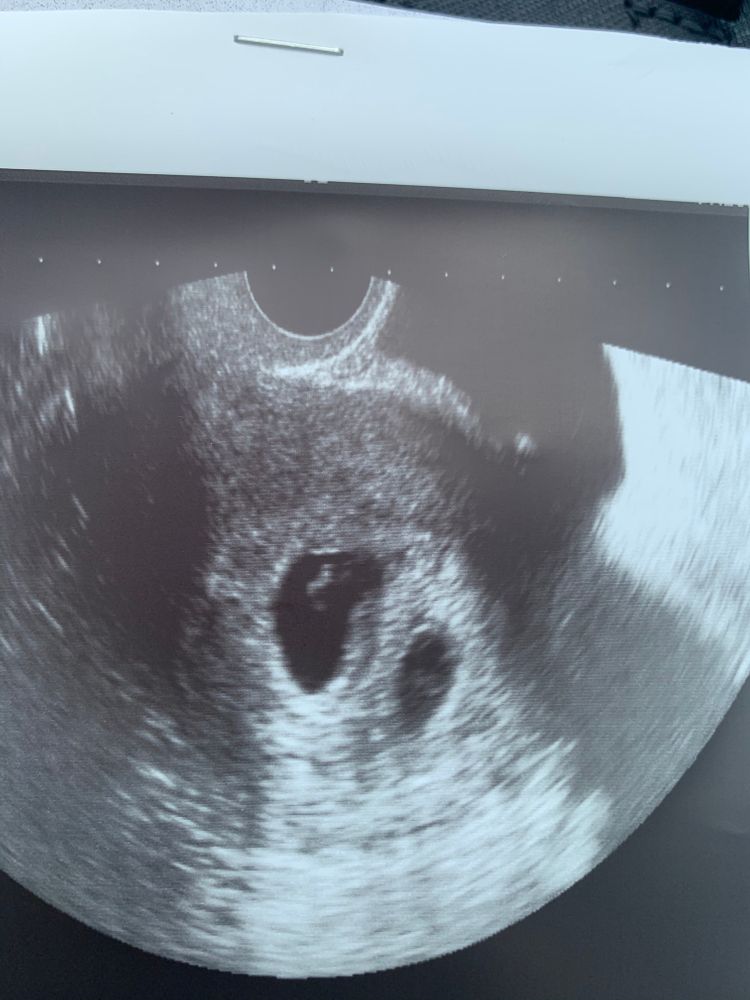

У меня не гематома была)) а реально второе пя и оно росло, а потом пошло на уменьшение)) Изображение Вот четко видно второе пустое..